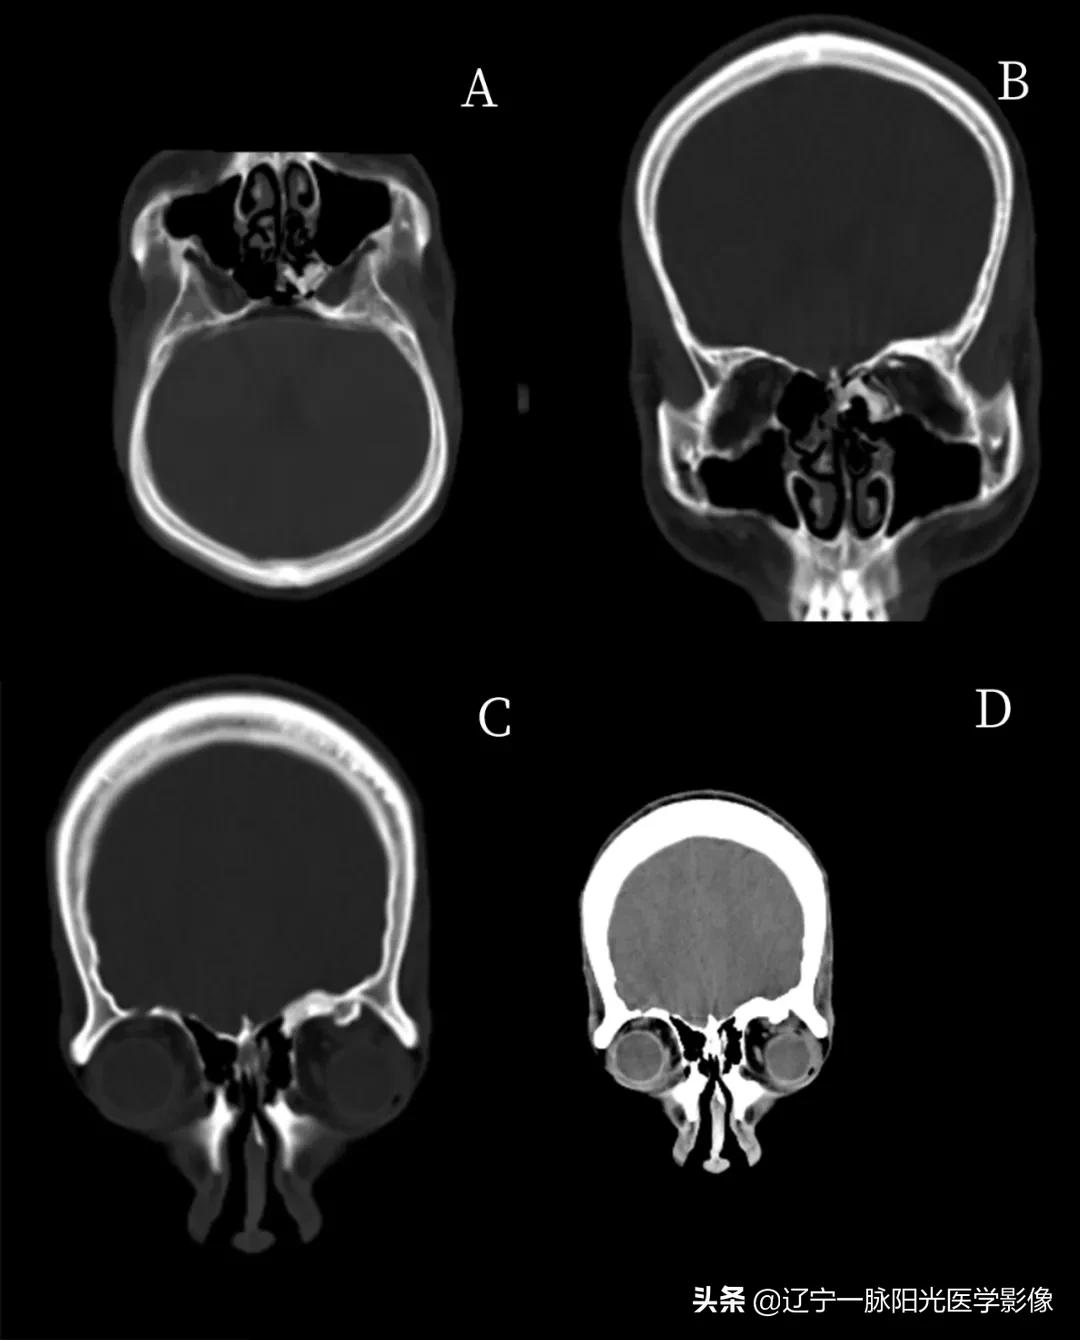

影像所见:

图 A、B 左侧筛窦外侧壁骨质不规则增厚,密度增高

图 C 示左侧眼眶上壁见向腔内突出的骨性密度影

图 D 冠状位软组织窗示左侧眼上直肌受骨样密度影压迫伴增粗,左侧眼球向前稍突出

最终诊断:左侧筛窦及左眼眶上壁骨瘤伴左眼上直肌受压、左眼球突出